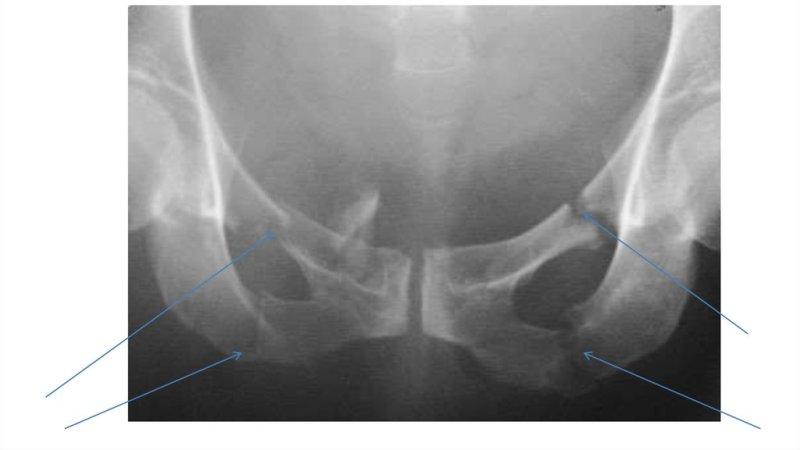

- рентгенография (обзорный снимок, изображение лобковой кости);

- МРТ и КТ (при необходимости).